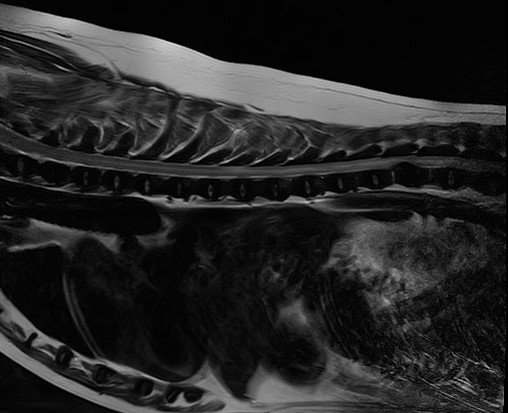

8才7ヶ月齢ミニチュアダックスフンド グレード5のT12-13椎間板ヘルニアです。病変部からT8までの脊髄はT2強調で高信号を呈しており、画像上、脊髄軟化症が強く疑われました。即日手術となり片側椎弓切除を実施したところ、硬膜には発赤が認められました。硬膜切開を実施したところ脊髄は軟化しており、後に病理組織検査で脊髄軟化症と診断されました